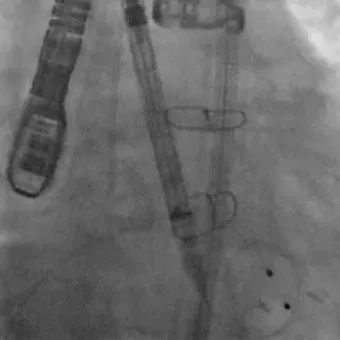

患者在全麻下进行手术,经右侧股动脉建立主入路,直头导丝跨瓣后交换预塑弯形导丝放置于左室。TaurusMax®经导管主动脉瓣系统装载AV29瓣膜,该系统具有“双轴”调弯功能,系统过弓跨瓣更加安全顺畅,同时系统在跨瓣后可实现同轴调整,降低术中对导丝操作的依赖,改善瓣膜释放不同轴导致的高低瓣问题,提升瓣膜释放稳定性及血流动力学。瓣膜在调弯状态下一次释放脱钩,瓣膜深度瓣下2mm,形态良好,同轴性佳,DSA下对合缘对齐(CA)结果良好。

调弯状态下稳定脱钩释放

最终造影